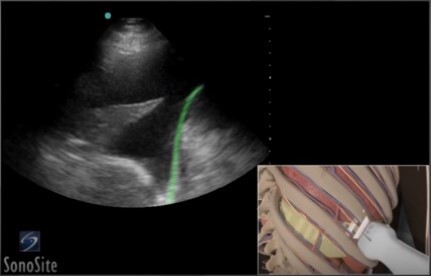

Thoracentesis Image

Highlighted Area: Diaphragm